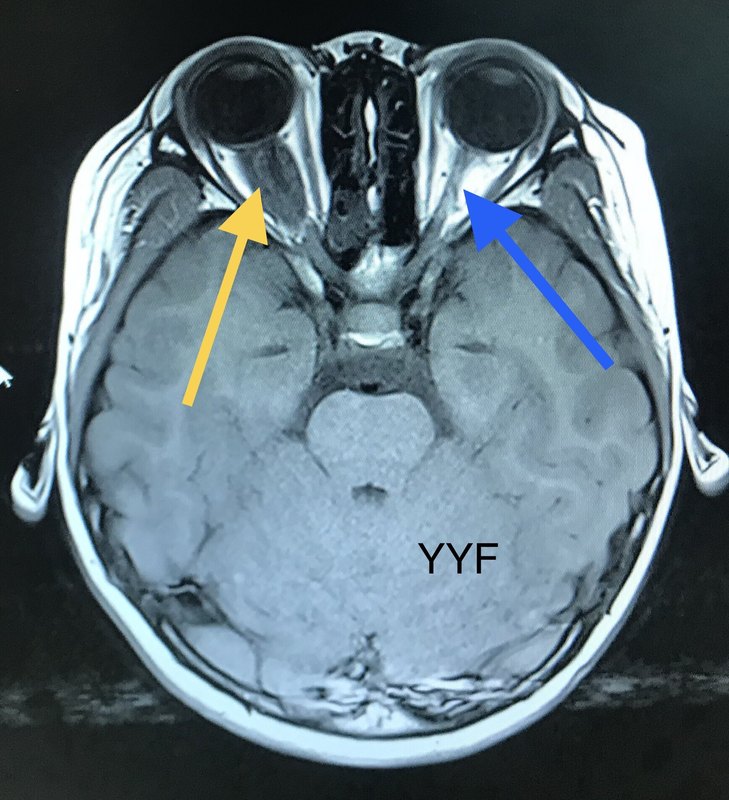

賀曉生教授:少年的“眼病”視神經(jīng)膠質(zhì)瘤

視神經(jīng)瘤治療分析:本病相對(duì)少見。瘤體可為單側(cè)、雙側(cè),可累及視交叉,甚至視束、視放射。患兒進(jìn)行性視力減退,瞳孔反射性擴(kuò)大,故患兒瞳仁多較大顯得又黑又亮。隨瘤體增大,視丘下部受累可出現(xiàn)多飲多尿表現(xiàn),腦室系統(tǒng)堵塞可伴發(fā)腦積水。瘤細(xì)胞以毛細(xì)胞型為多,發(fā)展緩慢。本瘤對(duì)化療和放療均不敏感。徹底的切除腫瘤,常會(huì)造成視力完全喪失,故不足以?。徊糠只顧z以明確診斷,是通常認(rèn)可的辦法。實(shí)際上,目前對(duì)視神經(jīng)膠質(zhì)瘤尚缺乏缺乏有效的保守型治療措施。我們祈禱這些患兒隨著醫(yī)療科學(xué)的進(jìn)步能有一天獲得視力的重生。 患兒,12歲,男。2010年就診時(shí),母親說孩子視力不好。檢查卻不是眼睛的問題,經(jīng)網(wǎng)上查詢找到賀教授,經(jīng)檢查發(fā)現(xiàn)孩子大大的眼睛,紅紅的臉頰,亮黑但顯得較大的瞳仁。 孩子頭顱MRI增強(qiáng)掃描顯示:雙側(cè)視神經(jīng)增粗、視交叉成結(jié)節(jié)狀。 賀曉生教授初步診斷:視神經(jīng)膠質(zhì)瘤。視神經(jīng)膠質(zhì)瘤能治療嗎?! 手術(shù)方案:少部分切除、明確診斷。 術(shù)后病理:視神經(jīng)毛細(xì)胞型膠質(zhì)瘤 隨訪情況:視力仍差,近距離視物。 視神經(jīng)瘤治療分析:本病相對(duì)少見。瘤體可為單側(cè)、雙側(cè),可累及視交叉,甚至視束、視放射?;純哼M(jìn)行性視力減退,瞳孔反射性擴(kuò)大,故患兒瞳仁多較大顯得又黑又亮。隨瘤體增大,視丘下部受累可出現(xiàn)多飲多尿表現(xiàn),腦室系統(tǒng)堵塞可伴發(fā)腦積水。瘤細(xì)胞以毛細(xì)胞型為多,發(fā)展緩慢。本瘤對(duì)化療和放療均不敏感。徹底的切除腫瘤,常會(huì)造成視力完全喪失,故不足以?。徊糠只顧z以明確診斷,是通常認(rèn)可的辦法。實(shí)際上,目前對(duì)視神經(jīng)膠質(zhì)瘤尚缺乏缺乏有效的保守型治療措施。我們祈禱這些患兒隨著醫(yī)療科學(xué)的進(jìn)步能有一天獲得視力的重生。本文系賀曉生醫(yī)生授權(quán)好大夫在線(bdsjw.cn)發(fā)布,未經(jīng)授權(quán)請(qǐng)勿轉(zhuǎn)載。